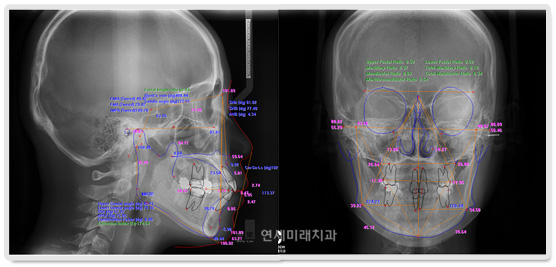

È¥ÇÕÄ¡¿±â ¾î¸°À̵鿡°Ô ÀÖ¾î¼, ¿µ±¸Ä¡°¡ ¸ÍÃâÇÒ °ø°£ÀÌ ºÎÁ·ÇÑ °æ¿ì °¡Àå ÈçÇÏ°Ô ³ªÅ¸³ª´Â Áõ»óÀº À§Åμ۰÷´Ï°¡ À߸ø ³ª¿À´Â °ÍÀÔ´Ï´Ù. À§ÅÎ ¼Û°÷´Ï´Â ¸¸ 11-12¼¼°æ¿¡ ¸ÍÃâÇÏ°Ô µÇ¸ç Å« ¾î ±Ý´Ï ¾ÕÂÊ¿¡¼´Â °¡Àå ³ªÁß¿¡ ³ª¿À´Â Ä¡¾ÆÀÔ´Ï´Ù. µû¶ó¼ À§Åο¡¼ ¿µ±¸Ä¡°¡ ³ª¿Ã °ø°£ÀÌ ºÎÁ· ÇÑ °æ¿ì »çÁø¿¡¼ º¸½Ã´Â °Íó·³ ¼Û°÷´Ï°¡ »ß¶Ô°Ô¸ÍÃâÇÏ°Ô µË´Ï´Ù. ¿µ±¸Ä¡°¡ ³ª¿Ã °ø°£ÀÌ ºÎÁ·ÇÑ °æ¿ì Ä¡·áÀÇ ÀÏÂ÷ÀûÀÎ ¸ñÇ¥´Â ¸ðµç ¿µ±¸Ä¡°¡ ±¸°³»·Î ³ª¿Ã ¼ö ÀÖ ´Â ȯ°æÀ» ¸¸µé¾îÁÖ´Â °ÍÀÔ´Ï´Ù. ¸ðµç ¿µ±¸Ä¡°¡ ±¸°³»·Î ¸ÍÃ⠵Ǿú´Ù¸é ¹Ù¶÷Á÷ÇÑ À§Ä¡¿¡ ¹è¿ ÇÏ°Ô µË´Ï´Ù. À̶§ ÇÊ¿äÇÑ °ø°£ÀÇ ¾ç, °ñ°Ý¹× ±³ÇÕ°ü°è, ³²¾ÆÀÖ´Â ¼ºÀå·®µîÀ» °í·ÁÇÏ¿© Ä¡·á¸¦ °áÁ¤ÇϰԵ˴ϴÙ.

¿µ±¸Ä¡°¡ ³ª¿Ã °ø°£ÀÌ ºÎÁ·ÇÏ´Ù°í ÇØ¼ ¹Ýµå½Ã ¹ßÄ¡¸¦ ÇØ¾ßÇÏ´Â °ÍÀº ¾Æ´Ï¸ç ¼ºÀåÀÌ ³²¾ÆÀÖ´Â ¾î¸°À̵éÀÇ °æ¿ì °ø°£À» È®º¸ÇÒ ¼ö ÀÖ´Â ¹æ¹ýÀÌ ¸¹±â ¶§¹®¿¡ »çÁø¿¡¼ º¸½Ã ´Â Áõ·Ê¿¡¼¿Í °°ÀÌ Ä¡¾Æ¸¦ »©Áö ¾Ê°íµµ ÁÁÀº °á°ú¸¦ ¾òÀ» ¼ö ÀÖ´Â °æ¿ì°¡ ´õ ¸¹ÀÌ ÀÖ½À´Ï´Ù.

¾Õ´Ï°¡ °Å²Ù·Î ¹°¸®´Â °æ¿ìÀÇ Ä¡·á¿¡ ÀÖ¾î¼ Áß¿äÇÑ °ÍÀº ¿øÀÎÀÌ °ñ°Ý°ü°è¿¡ ÀÖ´À³Ä, ±³ÇÕ°ü°è¿¡ ÀÖ´À³Ä ÇÏ´Â °ÍÀÔ´Ï´Ù. û¼Ò³âÀÇ °æ¿ì¿¡ ¼ºÀå´Ü°è¿¡ µû¶ó¼ ´Ù¾çÇÑ Á¢±Ù¹æ¹ýÀÌ ÀÖÀ¸¸ç, ¿øÀÎ ºÐ¼®¹× ÀÜ¿© ¼ºÀå·® Æò°¡ ÈÄ Ä¡·á¹æ¹ýÀ» °áÁ¤ÇÏ°Ô µË´Ï´Ù. ¾Õ´Ï°¡ °Å²Ù·Î ¹°¸®´Â ¼ºÀå±â ¾î¸°À̵éÀÇ °æ¿ì, Ä¡°ú¿¡ ³»¿øÇؼ °Ë»ç¸¦ ¹Þ¾Æ¾ßÇÏ´Â ½Ã±â´Â »çÁø¿¡¼ º¸½Ã´Â°Í ó·³ °Å²Ù·Î ¹°¸®´Â ¿µ±¸ÀüÄ¡°¡ ¹ß°ßµÈ Á÷ÈÄÀÔ´Ï´Ù. ¿Ö³ÄÇϸé ÀÌ ½Ã±â¿¡´Â °Å²Ù·Î ¹°¸®´Â ±³ÇÕ°ü°è ÀÚü°¡ ¾Æ·¡ÅÎÀÇ °ñ°ÝÀûÀÎ °ú¼ºÀåÀ» ÃËÁø½ÃŰ´Â ȯ°æÀÌ µÇ±â ¶§¹®ÀÔ´Ï´Ù. ¿µ±¸ÀüÄ¡´Â ¸¸ 7¼¼ ¹«·Æ¿¡ ¸ÍÃâµÇ´Âµ¥, ÀÌ ¶§ °üÂûµÇ´Â ÀüÄ¡ºÎ ¹Ý´ë±³ÇÕÀº °£´ÜÇÑ ¹æ¹ýÀ¸·Î ÇØ°áÇÒ ¼ö ÀÖ´Â °æ¿ì°¡ ¸¹½À´Ï´Ù.

°Å²Ù·Î ¹°¸®´Â ¿øÀÎÀÌ ½ÉÇѰñ°ÝÀûÀÎ ¹®Á¦¸¸ ¾Æ´Ï¶ó¸é ¹ÛÀ¸·Î º¸ÀÌ´Â ÀåÄ¡ ¾øÀ̵µ 6°³¿ù¿¡¼ 1³â »çÀÌ¿¡ »çÁø¿¡¼ º¸½Ã´Â Áõ·Ê¿¡¼ ó·³ ¹Ù¶÷Á÷ÇÑ ±³ÇÕ°ü°è¸¦ ´Þ¼ºÇÒ ¼ö ÀÖ½À´Ï´Ù.

¼ºÀÎÀÇ °æ¿ì¿¡ ¾Õ´Ï°¡ °Å²Ù·Î ¹°¸°´Ù°í ÇØ¼ ¹Ýµå½Ã ¾Ç±³Á¤ ¼ö¼úÀ» ÅëÇØ¼ Ä¡·áÇØ¾ßÇÏ´Â °ÍÀº ¾Æ´Õ´Ï´Ù. »çÁø¿¡¼ º¸½Ã´Â °æ¿ìó·³ °Å²Ù·Î ¹°¸®´Â ¿øÀÎÀÌ °ñ°Ý°ü°è°¡ ¾Æ´Ï°í ±³ÇÕ°ü°è¿¡ ÀÖ´Ù¸é ¼ºÀÎÀÇ °æ¿ì¿¡µµ ¼ö¼úÀ» ÇÏÁö ¾Ê°í ±³Á¤¸¸À¸·Î Ä¡·á°¡ °¡´ÉÇÕ´Ï´Ù.